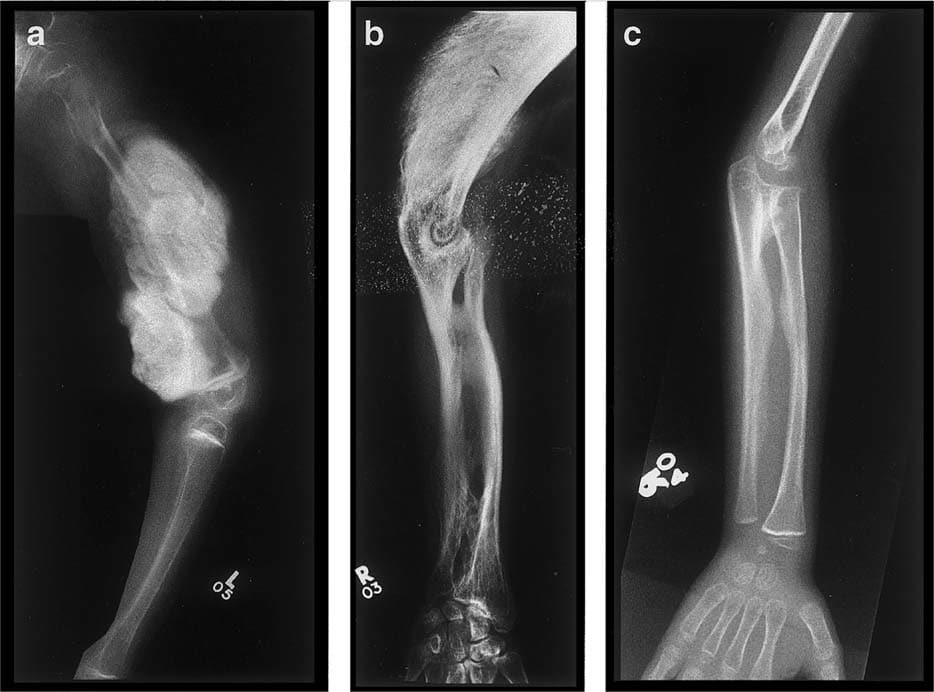

OI Tip V: 11. kromozomda bulunan IFITM5 genindeki heterozigot mutasyondan kaynaklanır. OI Tip V, orta şiddettedir ve görünüm ve semptomlar açısından Tip IV’e benzer. Belirgin özellikler arasında kırık veya cerrahi bölgelerde oluşabilen hipertrofik nasırlar ve radius ile ulna (ön koldaki 2 kemik) arasındaki zarın kireçlenmesi nedeniyle sınırlı önkol hareketi. OI V, otozomal dominant modelde kalıtılır.(5)(8)(9)